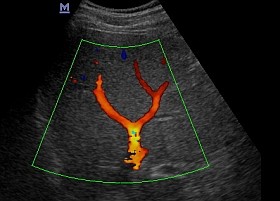

A szív-és érrendszeri problémák nem csak Magyarországon, hanem az egész világon népbetegségnek számítanak, melynek szövődményei a vezető halálokok közt szerepelnek. Éppen ezért érdemes panaszok esetén – illetve ha nagyobb kockázati csoportba tartozik- ellenőriztetni erei állapotát, hogy elkerülhesse a súlyosabb problémákat. Az artériák és a vénák ultrahangos vizsgálatáról dr. Szabó Andrea, az Ultrahang Központ radiológus főorvosa beszélt.

Ultrahangos vizsgálat lábfájdalom esetén és visszérműtét előtt is

Az erek állapotának megállapításához az egyik legjobb módszer a Doppler ultrahangos vizsgálat, mely során nem csupán az erek károsodásának fokáról kaphatunk pontos információt, de a bennük lévő keringésről, a vér áramlásáról is. A normál ultrahanghoz hasonlóan szintén fájdalommentes és nem igényel különösebb előkészületet, illetve semmiféle sugárterheléssel nem jár. A vizsgálat az érszűkület mértékének meghatározása mellett nagy segítségre lehet a vénabillentyűk állapotának megfigyelésében, valamint a mélyvénás trombózis diagnosztizálásában is.